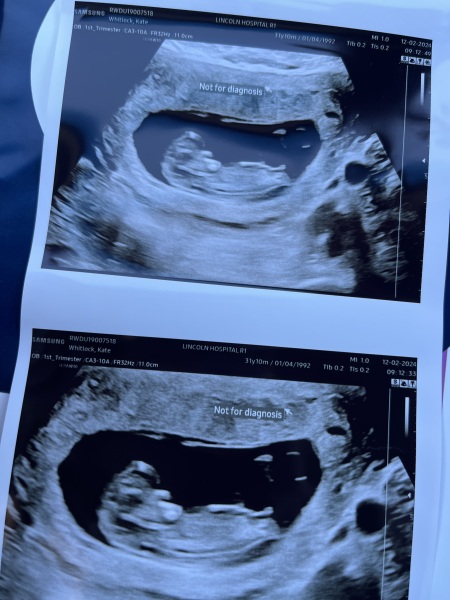

Kate543 · 12/02/2024 12:04

so I went for my nhs scan this morning and all was fine except measuring 11+1 and they have asked me to come back Friday so they can do the nt measurements 🤣

@Kate543 Aww beautiful scan!

Kate543 · 12/02/2024 14:21

@MrsB2019x thank you!

@siobhanmt247 maybe then! Apparently the baby has to measure 45mm and they measured 43.5 😂so a few more days and will be fine :) good news is just means get to see them again

Megan004 · 13/02/2024 00:06

@Kate543 aw what a lovely scan pic! Also bonus you get to go back for another peek 😂